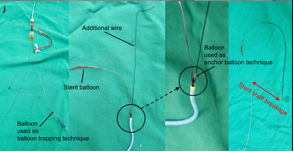

Yoshinobu Murasato, MD, PhD; Kyohei Meno, MD; Takahiro Mori, MD, PhD

An 83-year-old man who had undergone coronary aorta bypass graft surgery 25 years ago required treatment for new-onset worsening angina.